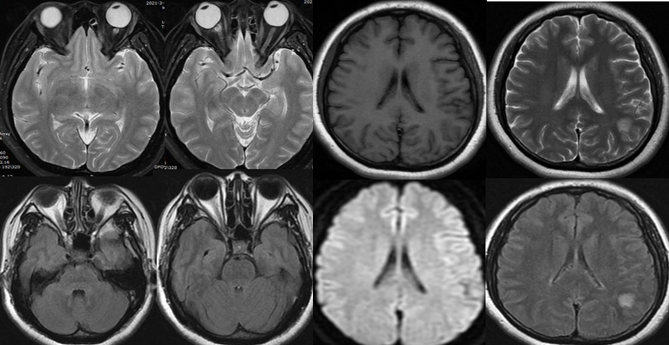

患者男,52岁,因“幻觉胡言 乱语3天,伴视物重影2天”入院。

答案:韦尼克脑病。易受到硫胺素(维生素B1)缺乏造成的损害的部位包括丘脑、乳头体、导水管周围和室旁区域、蓝斑、 颅神经核和网状结构。临床表现包括以下三个症状:眼肌麻痹、共济失调和脑病症状精神状态或智能状态改变。